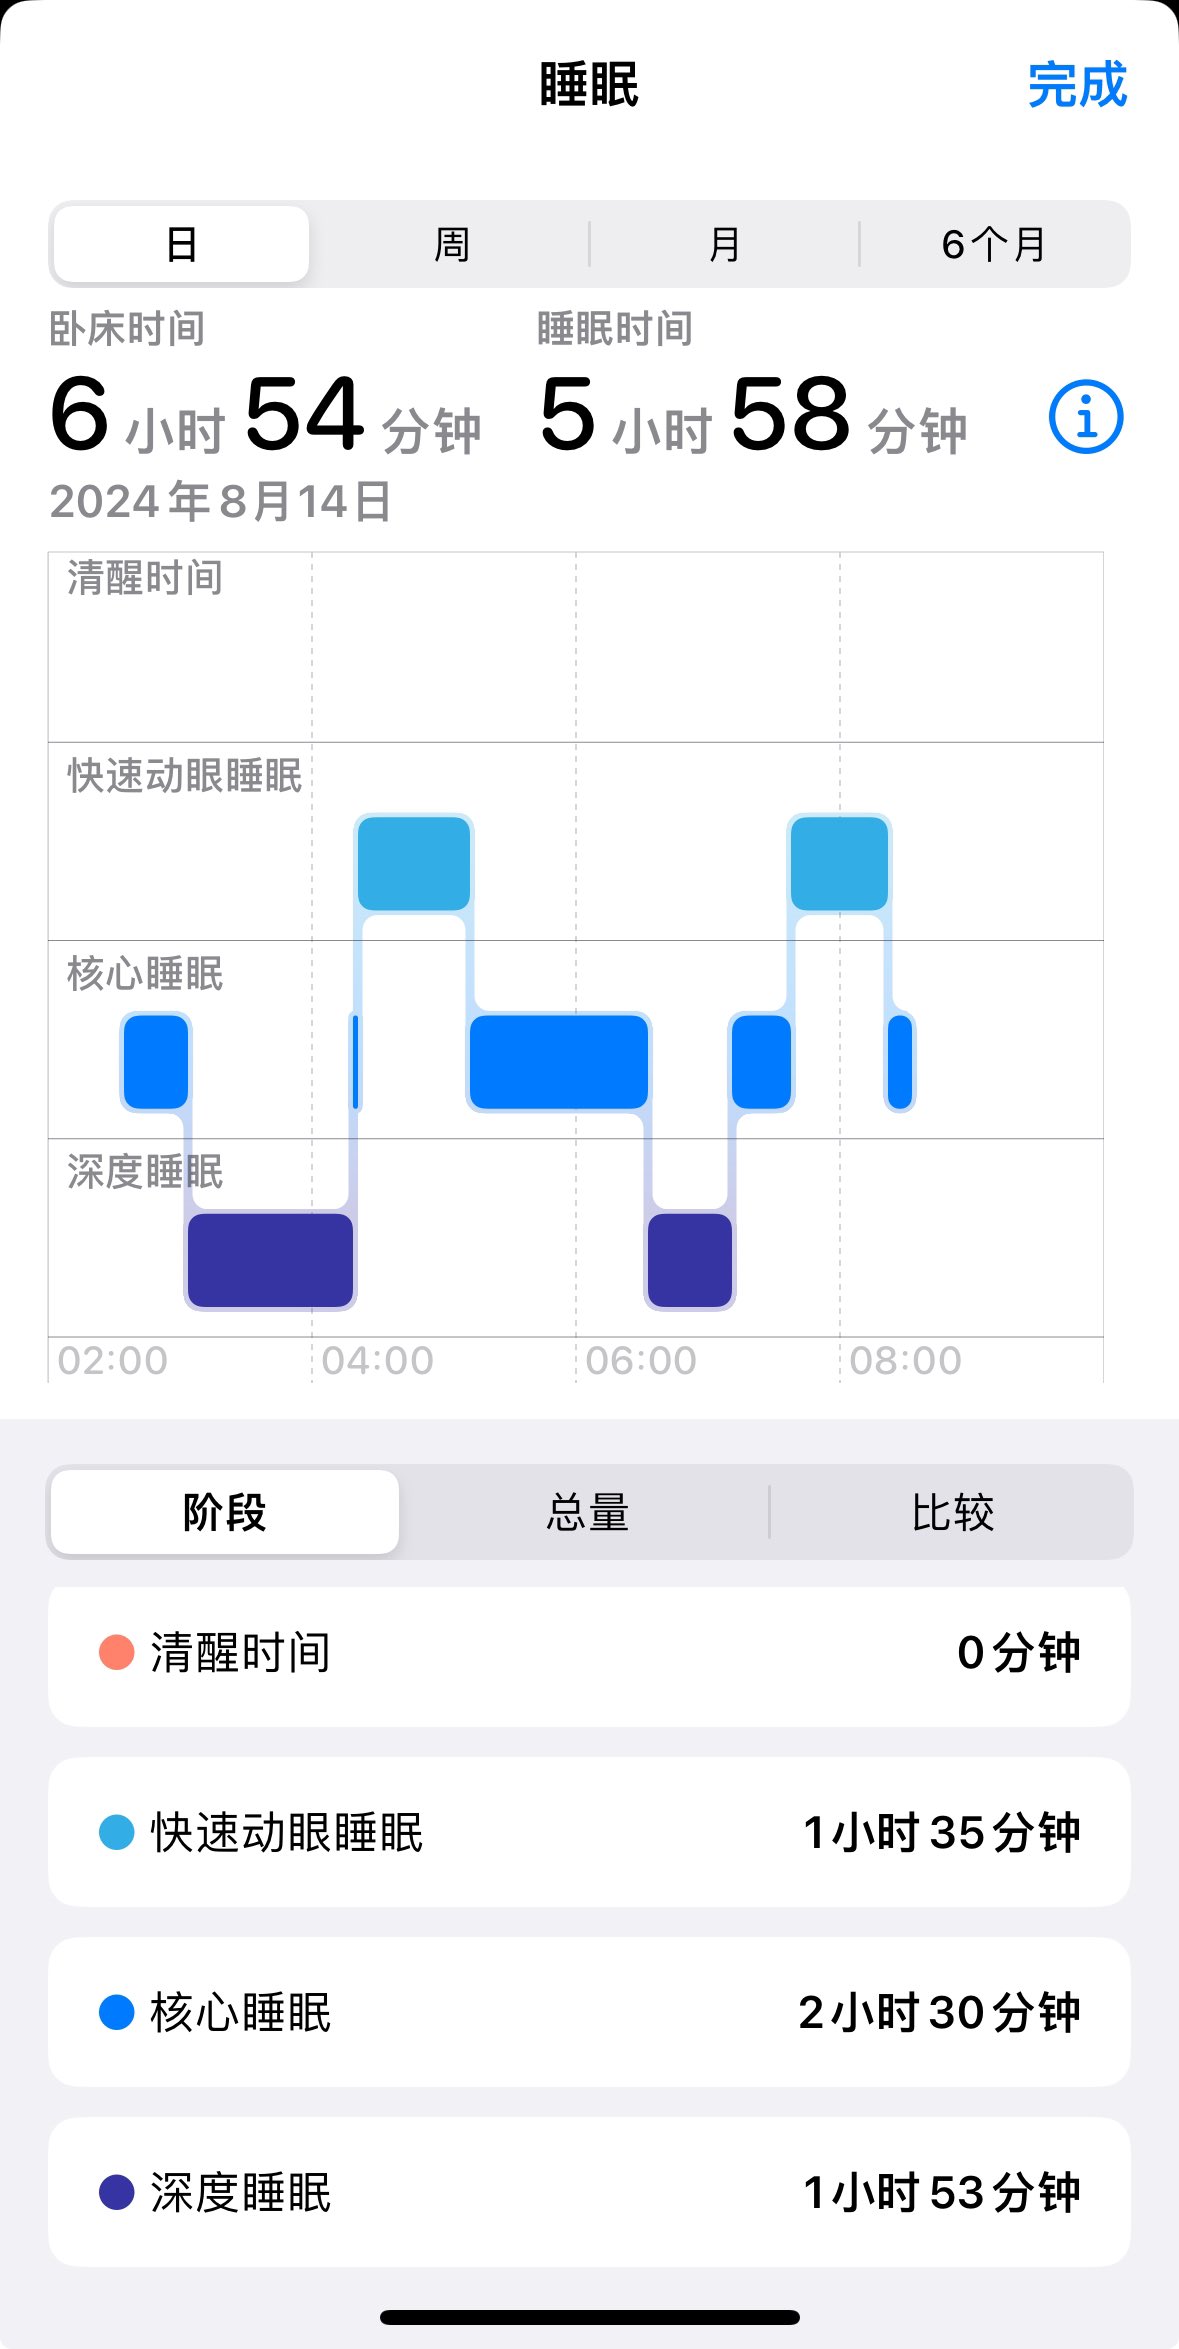

甚至在第二天有余晖的感觉,虽然发生了很多破事但没怎么影响心情*抗焦虑&镇静

此剂量下对睡眠的改善作用,增加了慢波睡眠且没有影响rem,精力恢复+

FDA数据,在临床剂量下(75-600mg)普瑞巴林的依赖性低于bzd,并相比之下它产生的认知和精神运动障碍较轻 https://t.co/TJ7ZOQ7pbC